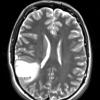

NEOPLASMS (GLIAL)

Astrocytoma, IDH-mutant, WHO Grade 2 (10)